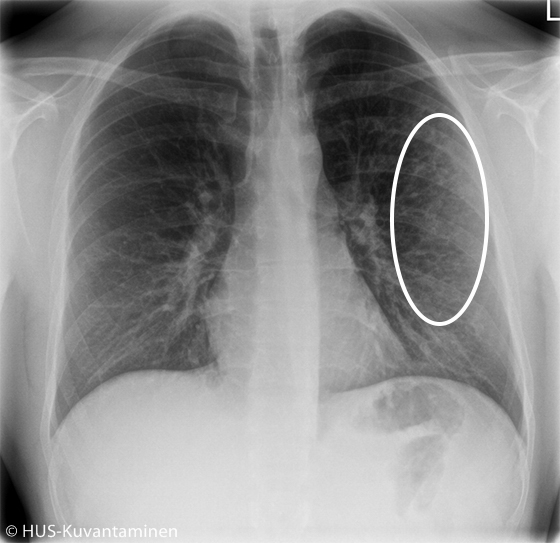

Atypical pneumonia in a patient with HIV (radiograph with markers).

The chest X-ray showed atypical pneumonia. There is diffuse shadowing and increased markings in the distal lung parenchyma (circle).